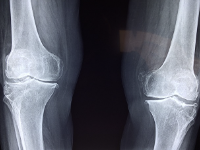

무릎 관절에 좋은 음식

무릎 관절은 우리 몸에서 가장 중요한 부위 중 하나이기 때문에, 무릎 관절 건강을 유지하기 위해서는 올바른 식습관을 유지하는 것이 중요합니다. 적절한 식습관을 통해 무릎 관절을 강화하고, 연골을 보호할 수 있습니다. 다음은 무릎 관절에 좋은 음식의 일부입니다.

- 생선: 오메가-3 지방산이 풍부한 물고기는 무릎 관절의 염증을 완화하고, 연골 손상을 예방하는 데 도움이 됩니다. 대표적으로는 참치, 연어, 고등어 등이 있습니다.

- 채소: 채소는 무릎 관절 건강에 필수적인 비타민과 미네랄이 풍부합니다. 특히, 녹색 채소와 당근, 고구마, 브로콜리 등의 채소는 무릎 관절염 예방에 효과적입니다.

- 과일: 과일은 항산화제와 비타민이 풍부하며, 무릎 관절의 염증을 완화하는 데 도움이 됩니다. 특히, 파인애플, 키위, 자몽 등의 과일에는 연골 생성에 중요한 성분인 효소가 들어 있습니다.

- 견과류: 견과류는 무릎 관절 건강에 도움이 되는 비타민과 미네랄이 풍부합니다. 특히, 호두, 아몬드, 땅콩 등의 견과류는 오메가-3 지방산이 풍부하여 무릎 관절 염증을 완화하는 데 도움이 됩니다.

- 우유 및 유제품: 우유와 유제품에는 칼슘, 단백질, 비타민 D 등이 풍부하며, 무릎 관절 건강에 도움이 됩니다. 특히, 요구르트는 프로바이오틱스를 포함하여 무릎 관절염 예방에 효과적입니다.

- 녹차: 녹차는 항산화제와 폴리페놀, 카테킨 등의 성분이 풍부하여, 무릎 관절의 염증을 완화하고, 무릎 관절염 예방에 좋습니다.

무릎 관절 관리 방법

무릎 관절 건강을 유지하고 관리하는 것은 무릎 관절염 예방 및 치료에 중요합니다. 다음은 무릎 관절 관리 방법에 대해 설명해드리겠습니다.

- 체중 조절: 과체중은 무릎 관절 부담을 높이고, 무릎 관절염 발생 가능성을 높입니다. 체중을 감량하여 무릎 관절에 가해지는 압력을 줄이는 것이 좋습니다.

- 적절한 운동: 균형 잡힌 운동을 통해 무릎 관절 염증을 예방할 수 있습니다. 하지만, 무릎 관절의 손상이 있는 경우, 무릎 관절에 더 큰 부담을 주는 운동은 지양해야 합니다.

- 무릎 관절 보호: 무릎 관절에 충격을 줄이기 위해 쿠션 매트와 같은 소프트한 표면에서 운동을 하는 것이 좋습니다. 또한, 무릎 패드를 착용하거나 신발 굽 높이를 조절하는 것도 무릎 관절 보호에 도움이 됩니다.

- 일상 생활에서의 조치: 무릎 관절을 보호하기 위해 일상 생활에서 몇 가지 조치를 취할 수 있습니다. 예를 들어, 계단을 오르거나 내릴 때는 양 손에 잡고 하는 것이 좋습니다. 길게 앉았다가 일어날 때는 무릎을 굽히지 않고 바로 일어서는 것이 좋습니다.

- 식습관 개선: 식습관 개선은 무릎 관절 건강에도 영향을 미칩니다. 무릎 관절 건강에 좋은 음식을 먹고, 과도한 알코올 및 담배를 피하며, 충분한 수면과 수분 섭취가 필요합니다.

- 필요시 의료진의 상담: 만약 무릎 관절염 증상이 나타나면, 의료진의 상담을 받아야 합니다. 의료진은 무릎 관절염 진단과 치료를 위해 필요한 검사와 치료 방법 등을 제시해줍니다.

무릎 관절 건강에 대한 관심과 적극적인 관리는 무릎 관절염 예방과 치료에 중요합니다.